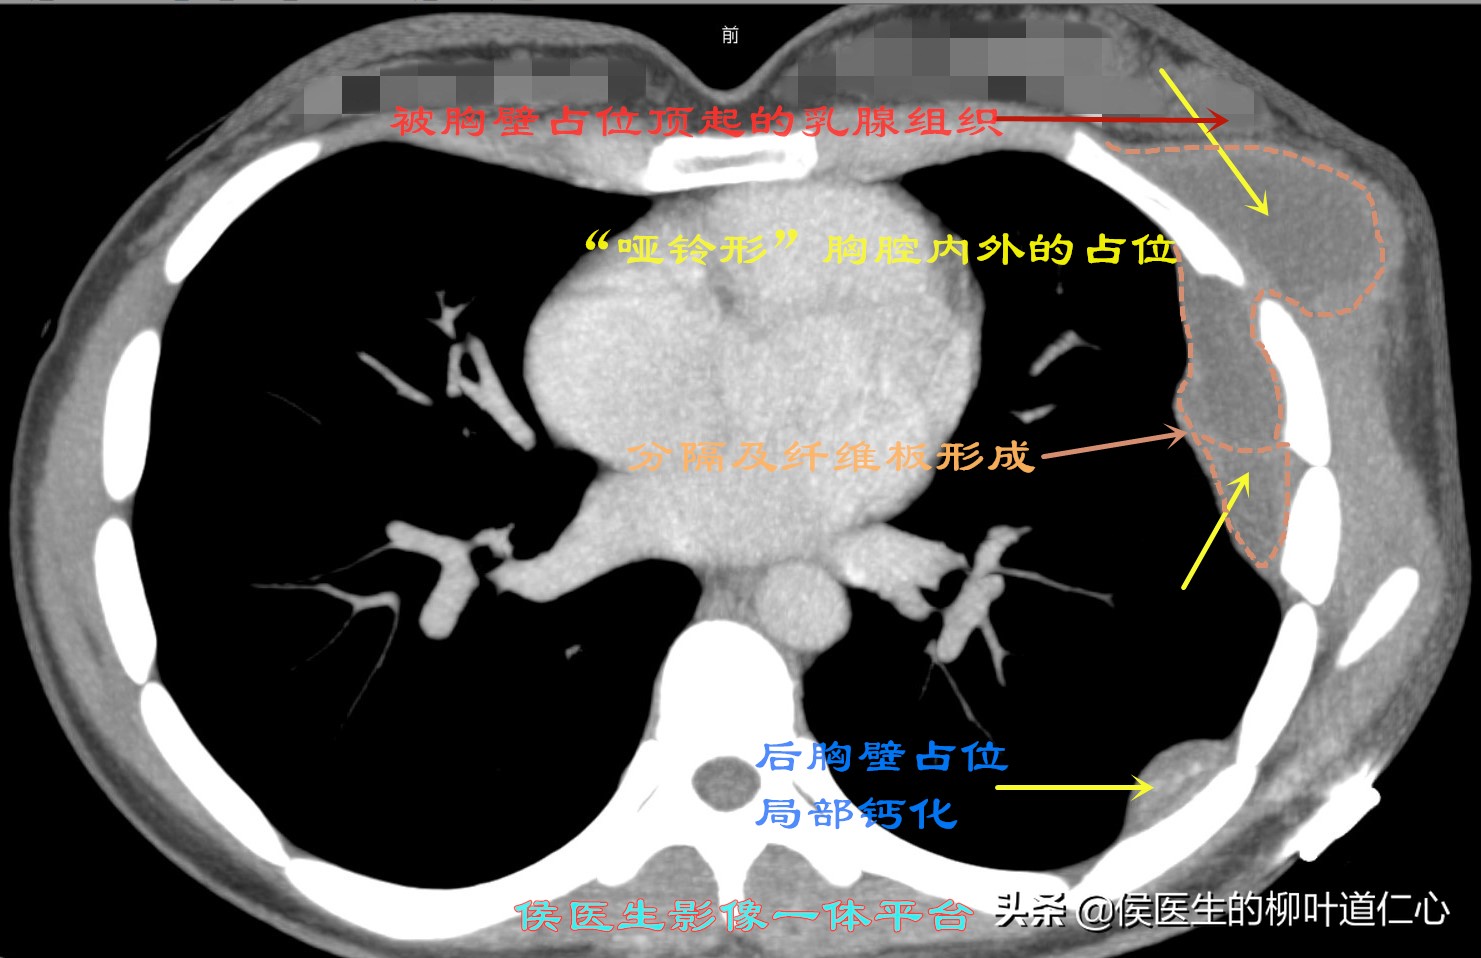

可以看到足以乱真的“乳腺占位”,但其实是位于肋骨外的富有囊壁的包块膨胀所为:

MPR重建,清晰地看到胸腔内外的结构如此相似,应该有着隐性的“通道”,如果仅仅处理胸壁病变,绝对的徒劳无功。

侯医生特地制作的动态影像,更能让您一目了然的理解,切除小段儿肋骨的必要性、清除胸腔内肺表面纤维板的重要性。